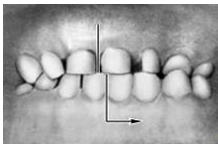

Прикус (occlusio) — соотношение зубных рядов при наиболее плотном смыкании зубов. Смыкание зубов верхней и нижней челюстей при различных движениях последней называется окклюзией. Откусывание и прожевывание пищи сопровождаются различными видами окклюзий. Откусывание осуществляется при передней (сагиттальной) окклюзии, когда смыкаются передние зубы, а боковые разобщаются (между ними появляется просвет). При жевательных движениях возникают боковые (трансверзальные) правая и левая окклюзии. Исходным и заключительным положением для всех жевательных движений нижней челюсти являются центральная (вертикальная) окклюзия, при которой линия, проходящая между центральными резцами обоих зубных рядов, совпадает со срединной линией лица.

Кроме аномалий П. в сагиттальной плоскости существуют аномалии П. в вертикальной и трансверзальной плоскостях. К основным вертикальным аномалиям (определяются по отношению к горизонтальной плоскости) относится открытый и глубокий П. Открытый П. (рис. 7, а) — наличие щели между зубными рядами при их смыкании, чаще в области передних зубов, реже в области боковых. Иногда смыкаются только последние моляры, что приводит к выраженным нарушениям жевательной функции и особенно речи. При глубоком П. (рис. 7, б) передние зубы одной из челюстей в значительной степени перекрывают коронки зубов-антагонистов, нижние резцы не опираются на зубные бугорки верхних резцов, а соскальзывают к их десневому краю, что приводит к постоянному травмированию десен и неба; нижняя часть лица укорочена за счет уменьшения или дистального положения подбородка.